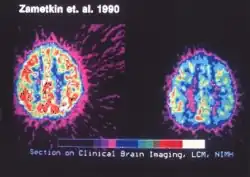

Estrutura cerebral

Em crianças com TDAH, verifica-se redução geral do volume em certas estruturas cerebrais, com diminuição proporcionalmente maior do volume do córtex pré-frontal esquerdo.[136][141] O córtex parietal posterior apresenta afinamento em indivíduos com TDAH em comparação com controles, e outras estruturas dos circuitos pré-frontal-estriatal-cerebelar e pré-frontal-estriatal-talâmico também diferem entre pessoas com e sem TDAH.[136][139][140] Os volumes subcorticais do núcleo accumbens, da amígdala, do caudado, do hipocampo e do putâmen parecem menores em indivíduos com TDAH.[142] Estudos com ressonância magnética estrutural também revelaram diferenças na matéria branca, com assimetria inter-hemisférica distinta entre jovens com TDAH e aqueles com desenvolvimento típico.[143] Estudos com fMRI evidenciam maior conectividade entre regiões subcorticais e corticais, como entre o caudado e o córtex pré-frontal, grau esse que se correlaciona com a gravidade da desatenção ou hiperatividade; processos de lateralização hemisférica também foram postulados, embora os dados empíricos sejam divergentes.[144][145][146]

Metilfenidato e anfetamina ou seus derivados são frequentemente tratamentos de primeira linha para o TDAH.[186][187] Cerca de 70% respondem ao primeiro estimulante testado e apenas 10% não respondem nem a anfetaminas nem ao metilfenidato.[163] Os estimulantes também podem reduzir o risco de lesões não intencionais em crianças com TDAH.[188] Estudos de ressonância magnética sugerem que o tratamento a longo prazo com anfetamina ou metilfenidato diminui anomalias na estrutura e função cerebrais encontradas em indivíduos com TDAH.[189][190][191]